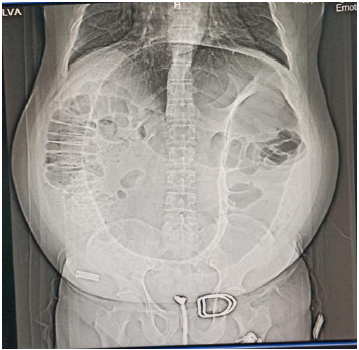

Um paciente de 60 anos de idade deu entrada no pronto-socorro sem acompanhante, com histórico de dor abdominal e parada de eliminação de flatos e fezes há três dias. Referiu que, no último mês, foi atendido duas vezes na mesma unidade, por episódios semelhantes. Ao exame físico, apresentou-se eupneico, estável hemodinâmicamente, com abdome globoso, timpânico à percussão, sem irritação peritoneal e com ECG 15.

Os exames laboratoriais evidenciaram leuco 7.000, Hb = 12 e creatina = 0,9, e o exame de raios X resultou na imagem a seguir.

Assinale a alternativa que indica a melhor conduta para esse caso nesse momento.

Com base no caso clínico apresentado, assinale a alternativa que corresponde à hipótese diagnóstica mais provavel.